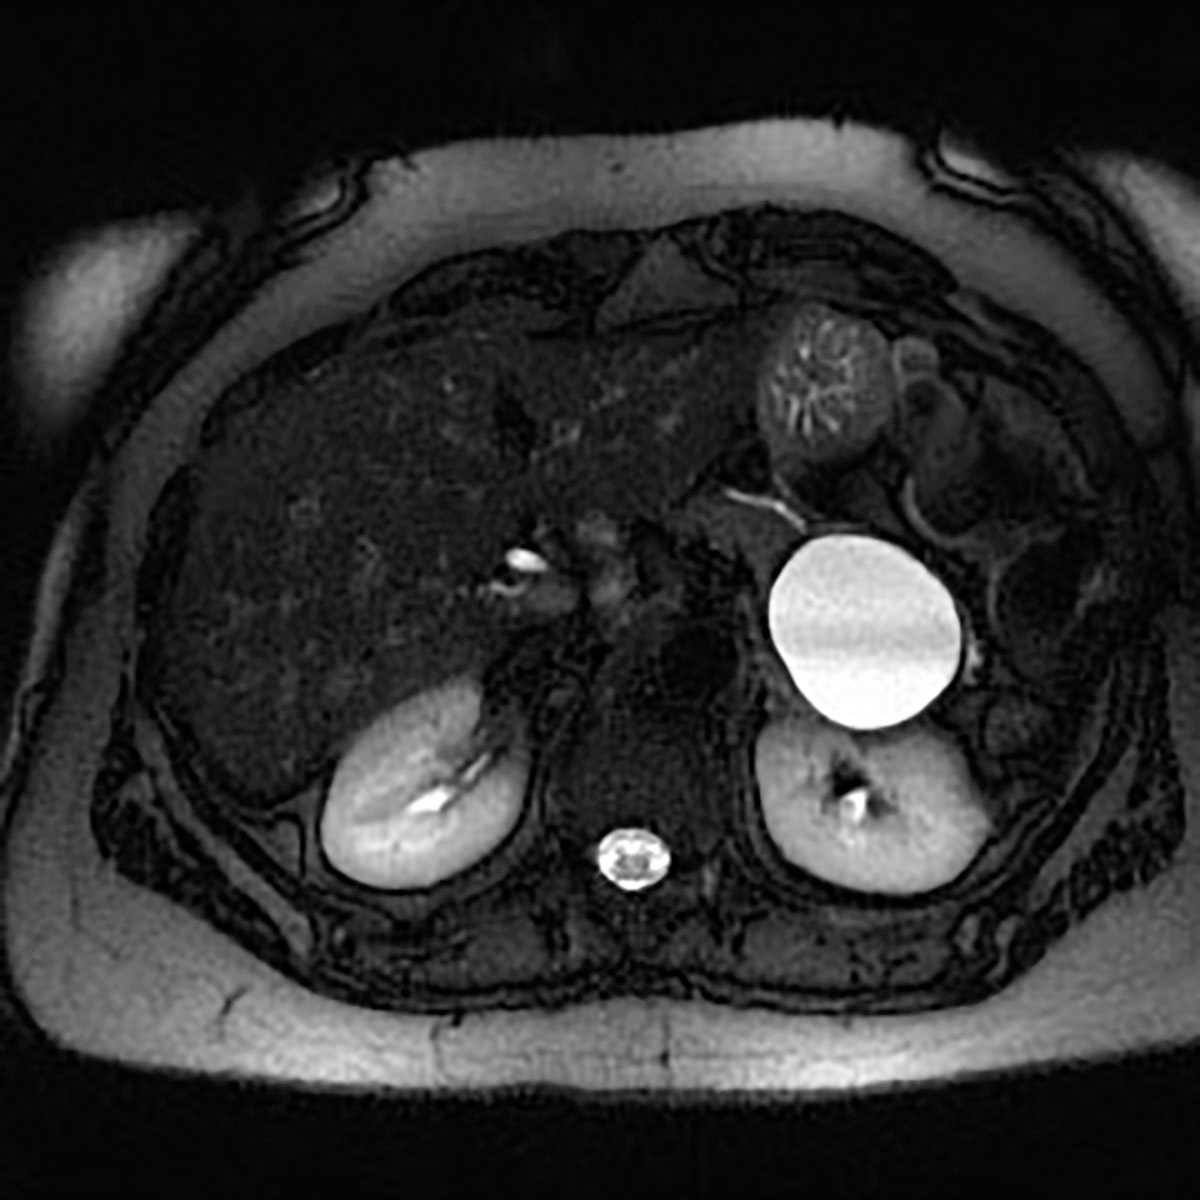

Carcinoma of the Head of the Pancreas